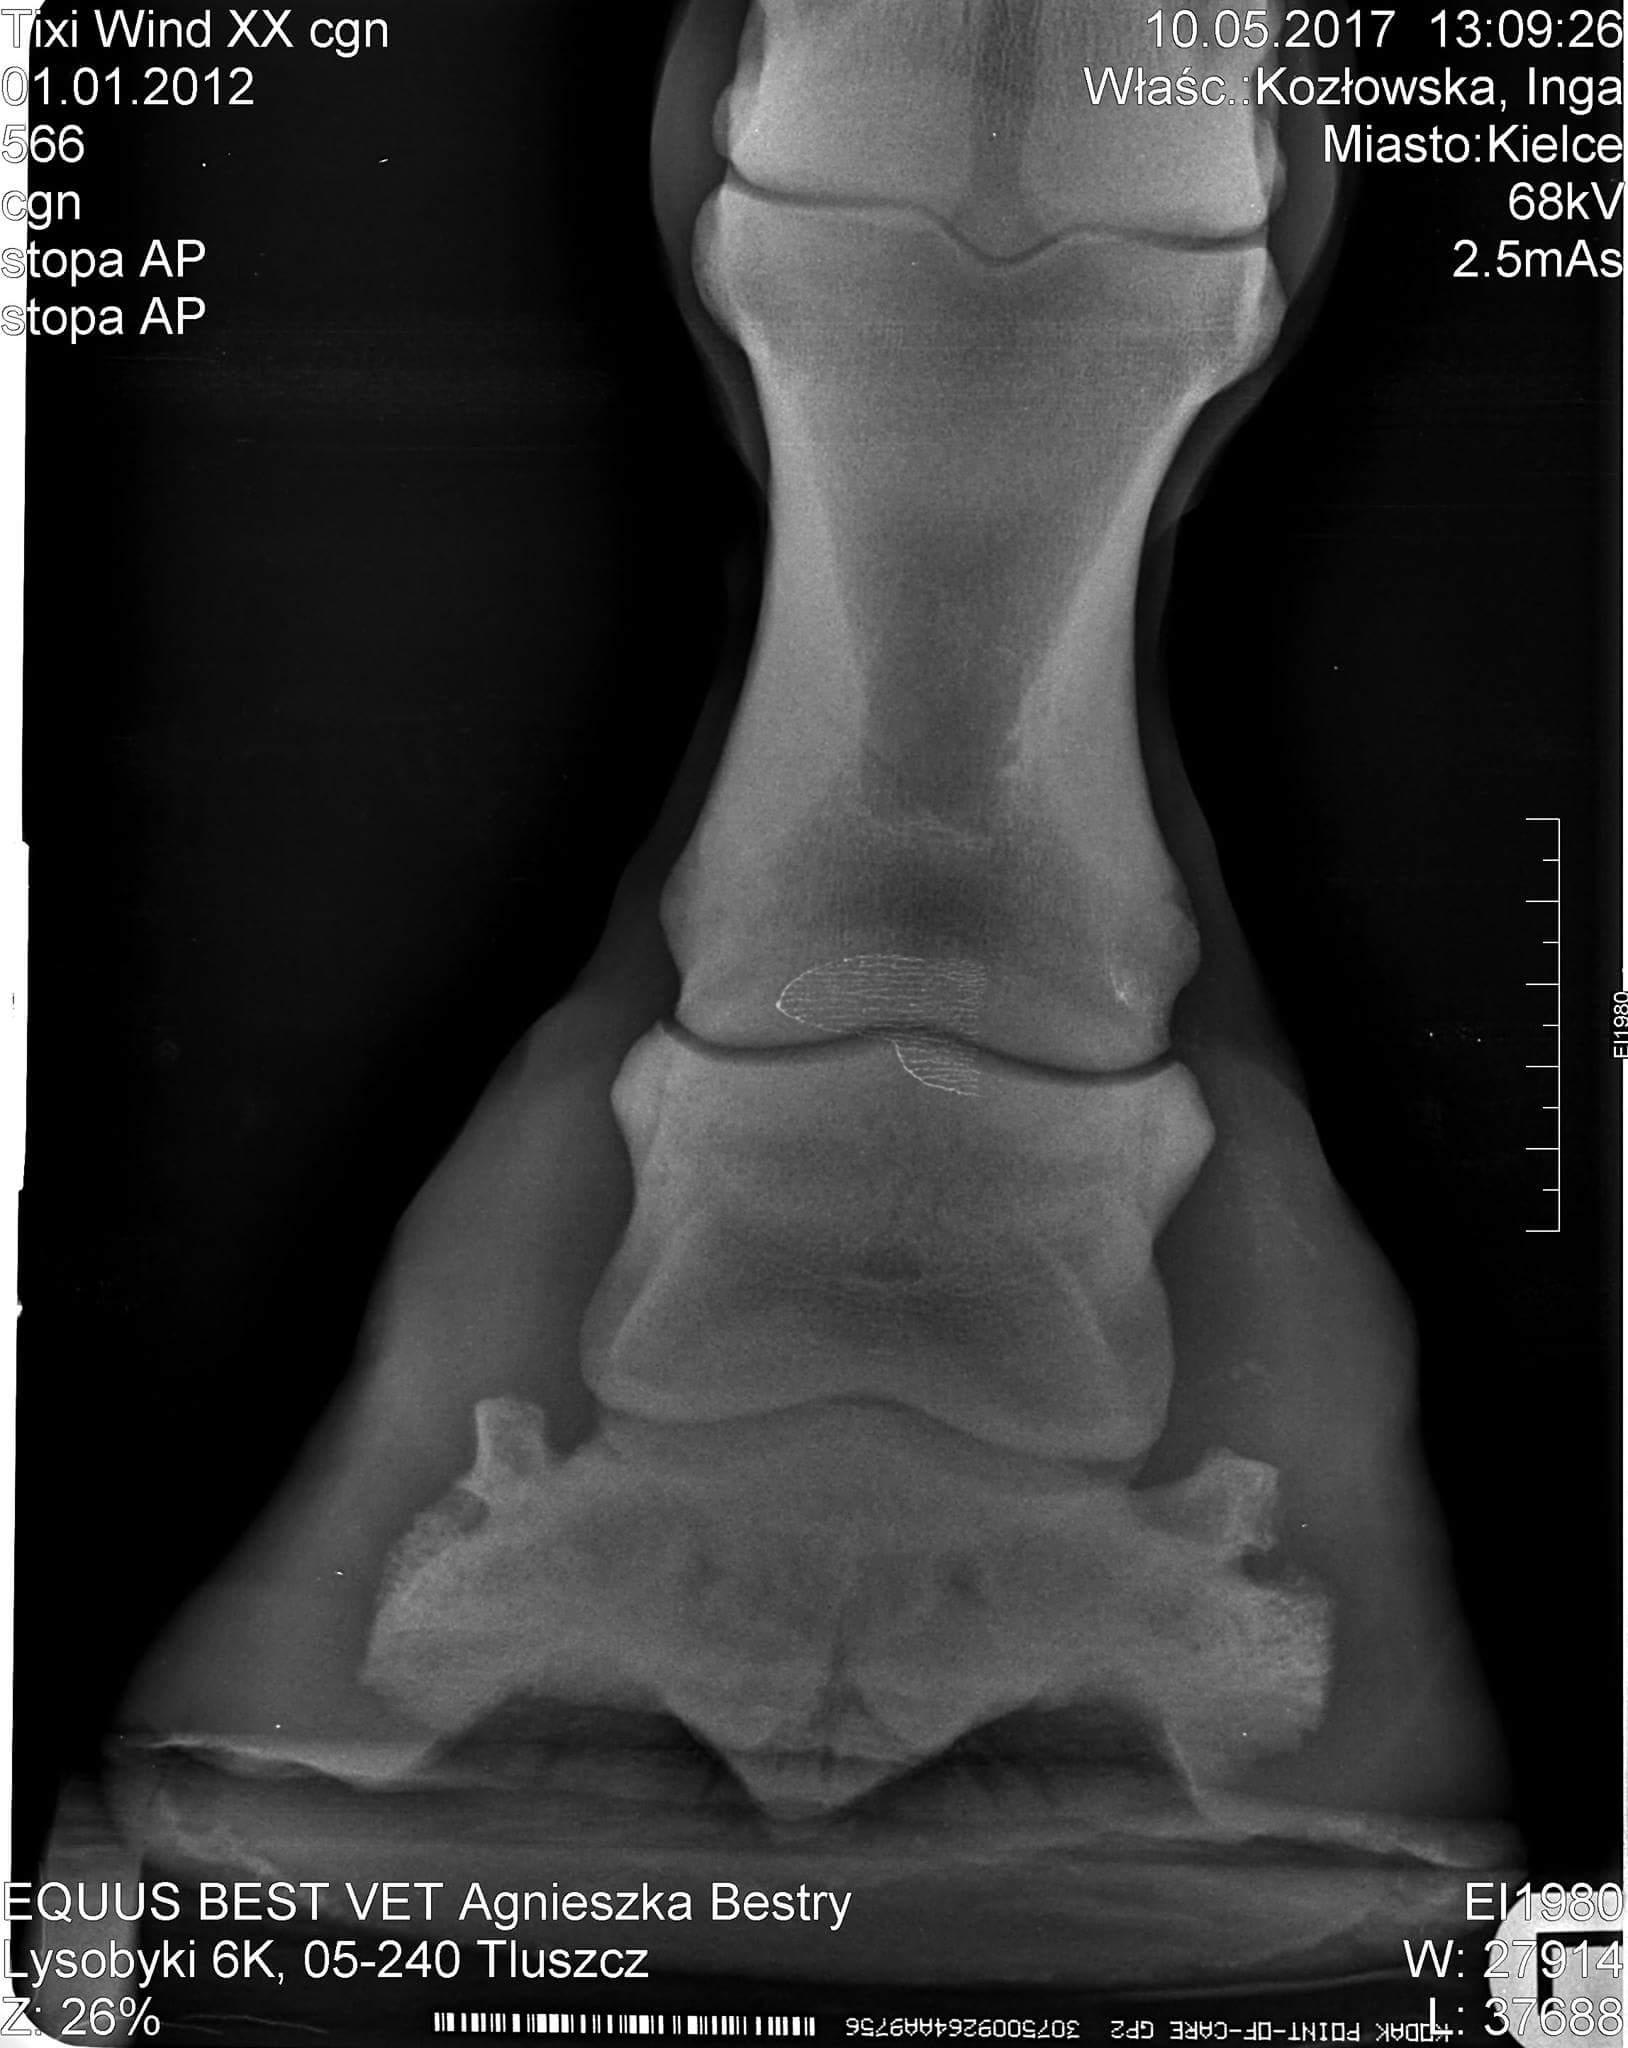

My 9 yo mare was diagnosed with navicular syndrome. Could you please take a look at those x-rays to See if you can also tell its navicular syndrome or maybe something else? Just want to double check while we are waiting for another vet. Thank you so much

Hi there. To me it looks like sidebone. Here is the link to an article about sidebone in horses: http://www.clydevetgroup.co.uk/equine/newsletters/dec07.htm I think the navicular bone itself looks OK to me however, when I zoom into the photo some detail is lost and it makes it difficult to evaluate. Also, you don't have all the x-ray views here for me to throughly evaluate the navicular bone. There should be a lateral view. That being said, I see no cones, lollipops or cysts on the navicular bone which are all things you can see with that disease process. Without knowing much of the history and what tests your vet has or has not done - just going on these x-rays - I would say the problem is sidebone. I hope this helps. Best wishes to you.